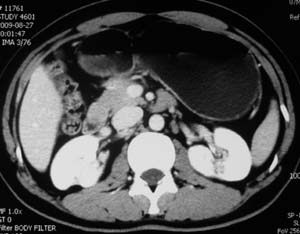

以下是引用子期在2010-3-19 20:47:00的发言:[br]血管畸形的ct增强应该有明显强化,本例并不相符合。本例双肾局部的略低密度影,累及肾盂,局部皮质明显变薄、内陷,增强扫描有轻度的强化,应考虑为炎性病变,患者为年轻男性,累及双肾的感染以结核较常见,可以没有明显的临床症状,尿中有时候也并不能查出什么;肾脓肿常有明显感染中毒症状,本例不符,另外一般的肾盂肾炎或肾小球肾炎通过小便就可确诊,其它还不能排除的是黄色肉芽肿性肾盂肾炎,然而单凭ct一般也很难鉴别。